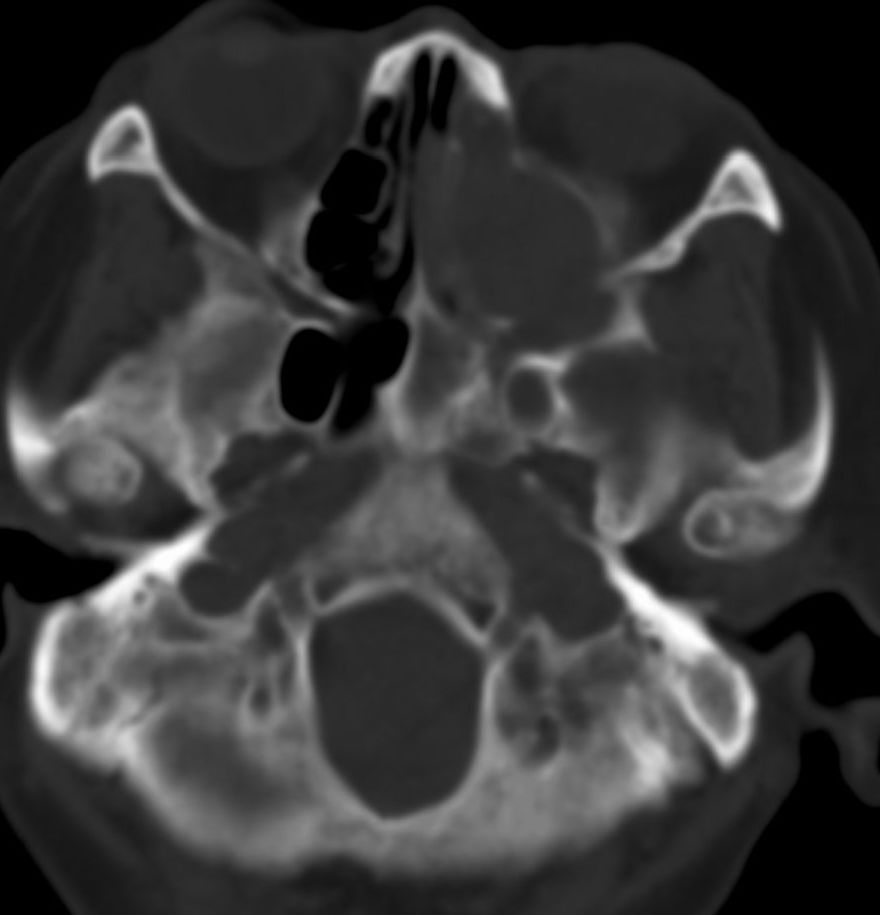

女,69岁。鼻出血2月多。(会诊病史就这样简单)鼻副窦ct检查如下:

左侧鼻腔及上颌窦见软组织块影,左侧上颌窦腔扩大,骨质吸收,右侧上颌窦见半圆形软组织密度影,鼻中隔向右侧弯曲,左侧鼻和鼻窦内翻型乳头状瘤可能性大,建议增强。

左侧上颌窦及鼻腔内见软组织密度影,其内密度不均匀,见斑片状高密度影,右侧上颌窦腔明显扩大,窦壁吸收变薄,鼻中隔右偏,右侧上颌窦见一半圆形软组织密度影,边界清楚,其内密度均匀。诊断,1、左侧鼻腔及上颌窦内翻乳头状瘤可能性大,上颌窦癌,息肉及霉菌性上颌窦炎待除外。2、右侧上颌窦粘膜下囊肿。

窦腔密度不均匀增高,无明显钙化征象,后外侧及内侧窦壁膨胀明显,局部破坏消失,筛窦受累及,但双侧对比发现左侧窦壁骨质有硬化增白现象,这可能是支持左侧霉菌性上颌窦炎的主要依据点。